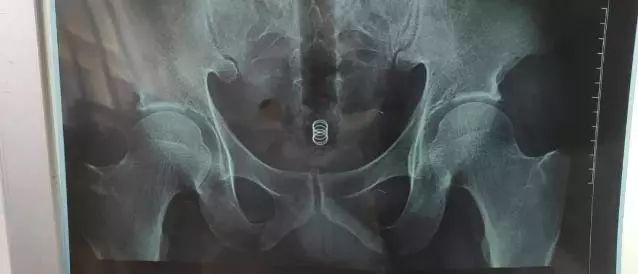

随后,医生给其进行了拍片。片子显示,该男子从肛门进入直肠的,是一长条类管子

菊花一紧!男子洗澡摔倒,面霜棒插入肛门!进去容易出来难…

并且可以从片子上看出,体内异物已深深陷入直肠,如果不及时处理会导致直肠感染,肠梗阻,肠穿孔等一系列并发症,甚至危及生命